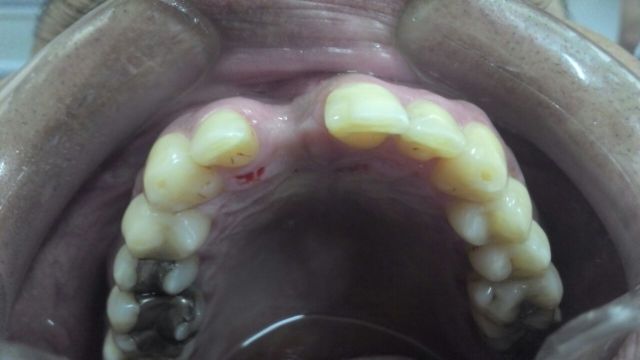

Veja o resultado

Veja como conseguimos recuperar todo o volume perdido, toda a estrutura normal.

Nessa foto podemos ver também o implante já instalado, que nesse caso foi possível realizar simultaneamente ao enxerto.

Nessa vista frontal, percebam a beleza e a naturalidade da gengiva recuperada. Notem toda a estrutura refeita perfeitamente tanto em quantidade como em posicionamento.